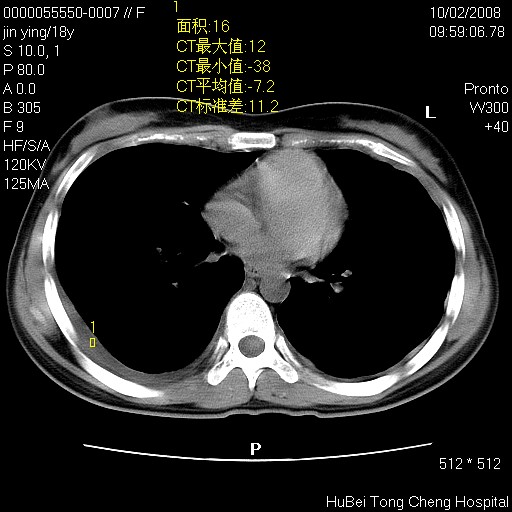

患者 女,18y。发热十余天,伴咳嗽。pe:t39⒈℃,bp 110/80mmhg,p 86次/min。神清,精神欠佳。双肺可闻及少许湿罗音。既往史不详。

临床诊断:肺部感染?

胸部ct轴位平扫(层厚10mm,螺距1.5,重建间隔10mm),图像如下: